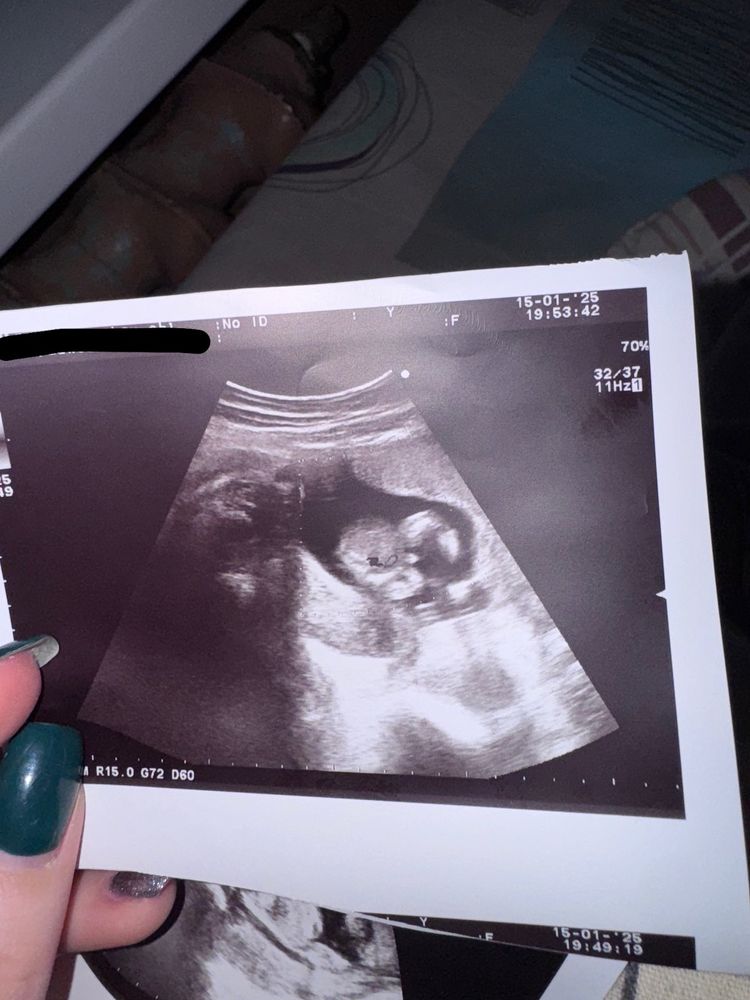

Здравствуйте, узи сделано на 16 Нед бер.

врач дал это фото и сказала что пацан.

что видите вы? Пацан или девочка? Или может всё таки это пуповина?

Я прям четко вижу мальчика))

Мальчик

У девочки как орешек ( два полукруга вместе )

А у мальчика как на фото - чуть выходит наружу

В 16 нед уже хорошо видно. Если врач сказал, что мальчик, значит так и есть

Я так понимаю это фото снизу и виден что-то типо писюнчика, но у меня почему-то сомнения